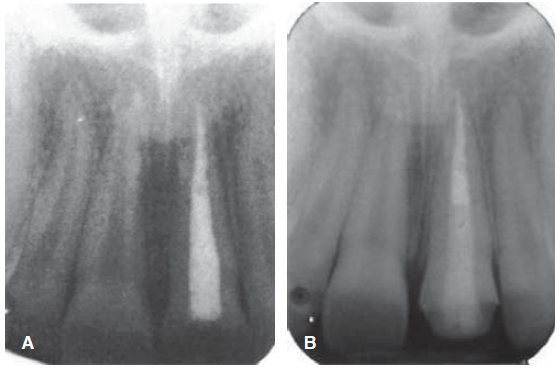

En la exploración clínica extra e intraoral sólo se observa la fractura dental (Figura 26), en la radiografía se observa el tratamiento de sistema de conductos (Figura 27).

Fractura complicada de corona del diente 21, radiográficamente se observa un diente despulpado con tratamiento de sistema de conductos y sin lesión periapical; periodontalmente presenta gingivitis inducida por placa dentobacteriana (Figura 28).

Desobturación con instrumentos de compactación vertical de Schilder, tratando de sellar mejor al momento de termoplastificar la gutapercha, se toma radiografía control de desobturación, observando que el Drill del sistema a utilizar queda con espacios (Figura 29 A), se ajuste del poste de fibra de vidrio FRC Postec ® Plus tamaño 3, de la casa comercial Ivoclar Vivadent, cuyo diámetro coronal es de 2 mm y el apical de 1 mm (Figura 29 B). Se corta el poste de fibra de vidrio en una intensión con pieza de alta velocidad, fresa de diamante grano grueso y abundante irrigación, luego se graba, se lava, se seca el conducto y se cementa el endoposte de fibra de vidrio con la parte coronal del mismo hacia apical del conducto para de esta forma ser más congruentes con el diámetro de un diente joven y el excedente apical del poste se introduce como poste complementario en coronal del conducto, la cementación y reconstrucción coronal se realizó con el sistema del cemento resinoso Rebilda DC ® (VOCO), finalmente se toma una radiografía control de cementación (Figura 29 C).

Figura 29 A) Desobturación. B) Prueba del poste de fibra de vidrio. C) Cementación del poste de fibra de vidrio.